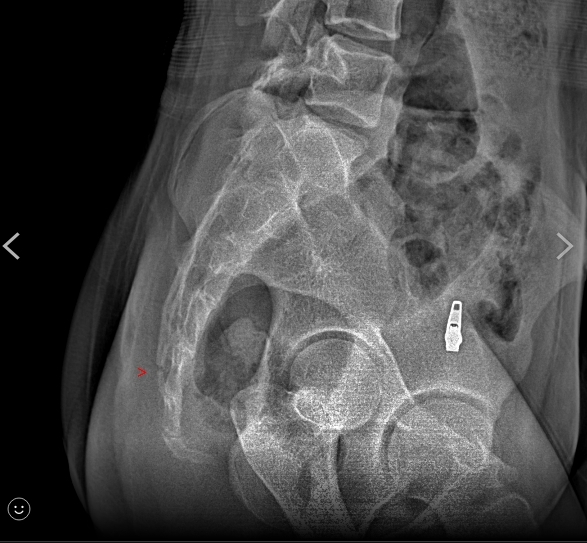

「她是這個地方裂了!」秀出X光片,還有受傷照,表面明顯瘀青,診斷證明書寫著,臀部挫傷,尾骨骨折,讓家長一看超心疼,要調閱監視器、釐清真相,但從11月25號發生至今,已經7天,學校遲遲沒有回應。不過校方祭出4點聲明說,練習場地在藝文中心舞台上,地板材質是礦石卡扣地板,有彈性,鋪防護墊容易滑,反而造成抬舉的學生受到更嚴重的傷害,才沒有使用防護墊,後續會尋覓合適場地,也會避免做抬舉動作,對於學生受傷,表達遺憾。